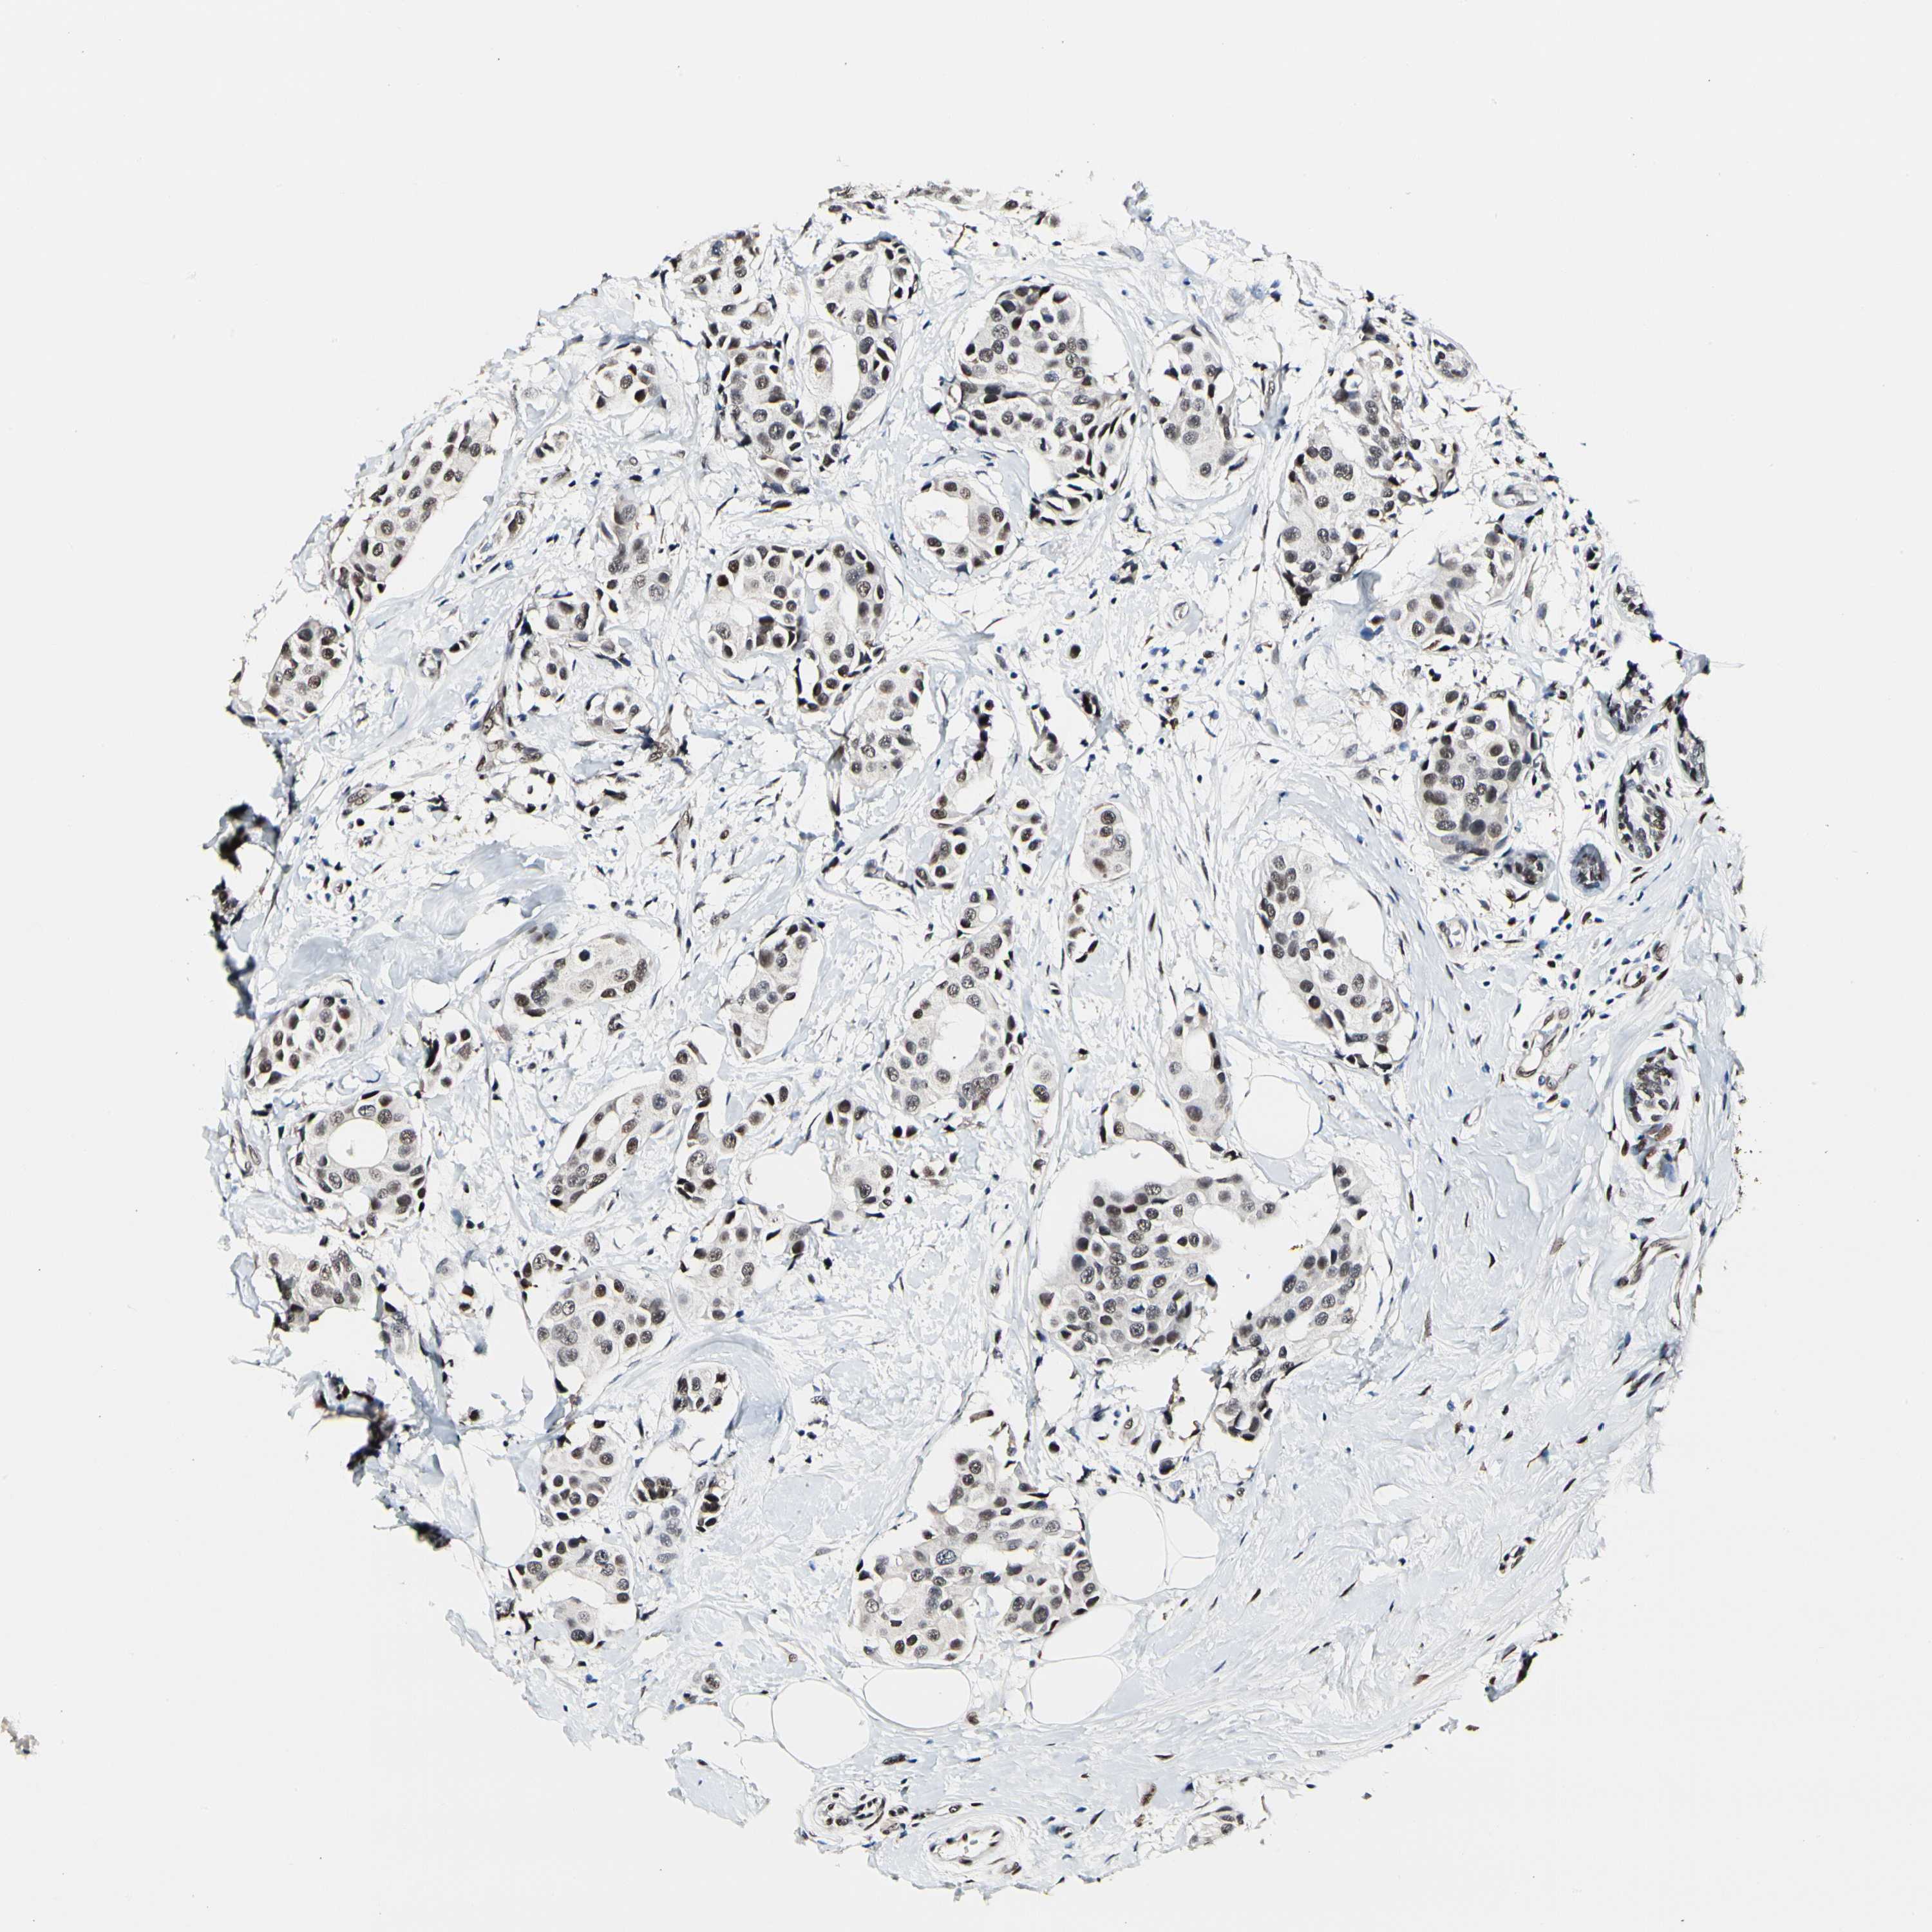

CANCER BREAST CANCER Show tissue menu

BRCA TCGA BRCA VALIDATION PROTEIN EXPRESSION